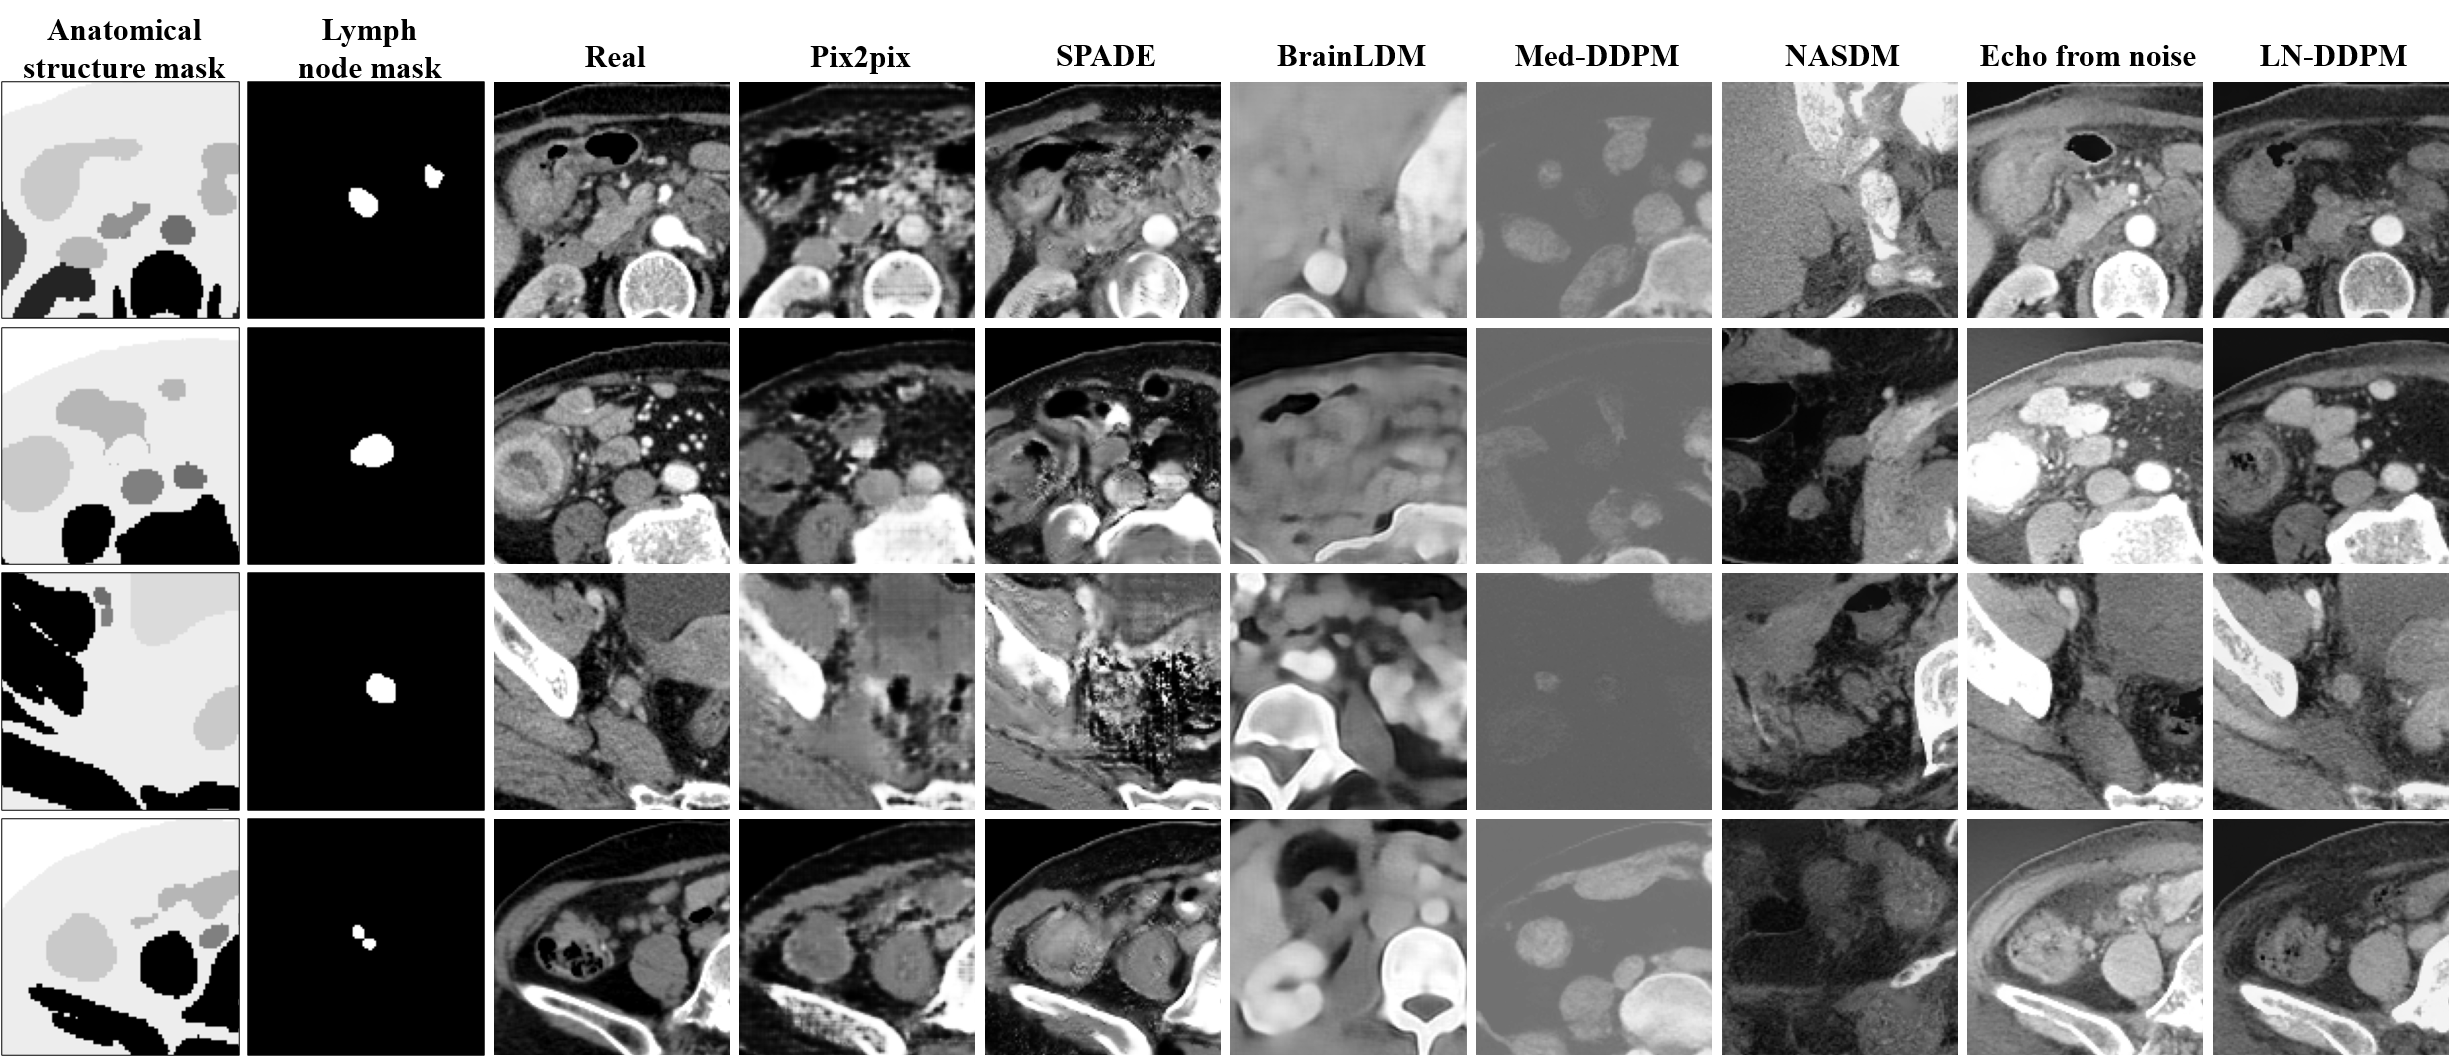

Fig. 4 visualizes the generation results of baseline methods and the proposed method under their respective sampling conditions. The third column displays the real abdominal lymph node images. Without anatomical structure mask as model condition, BrainLDM, Med-DDPM, and NASDM struggle to capture abdominal anatomical structure distributions. The abdominal lymph nodes generated by these methods are difficult to distinguish from other abdominal regions. Pix2pix, SPADE, Echo from noise, and LN-DDPM generate abdominal lymph node images that follow the realistic abdominal anatomical structures. The abdominal lymph node images synthesized by Pix2pix and SPADE, appear fuzzy and artificial compared to Echo from noise and LN-DDPM. Moreover, LN-DDPM generates abdominal lymph node images with more clear boundaries, especially the lymph nodes.